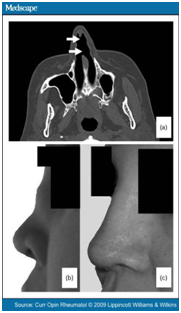

Wegner’s granulomatosis

- A condition characterized by granulomatous inflammation involving the respiratory tract and necrotizing vasculitis affecting small to medium sized vessels.

- The pathological hallmark is the co-existence of vasculitis and granulomas and classically involves a triad of airway, lungs and renal disease.

- Destruction of intranasal structures including septum may follow leading eventually to nasal collapse.

Diagnosis

- cANCA test is positive in 95% of patients.

- Mucosal thickening

- Bone destruction

- New bone formation

- Augmentation rhinoplasty